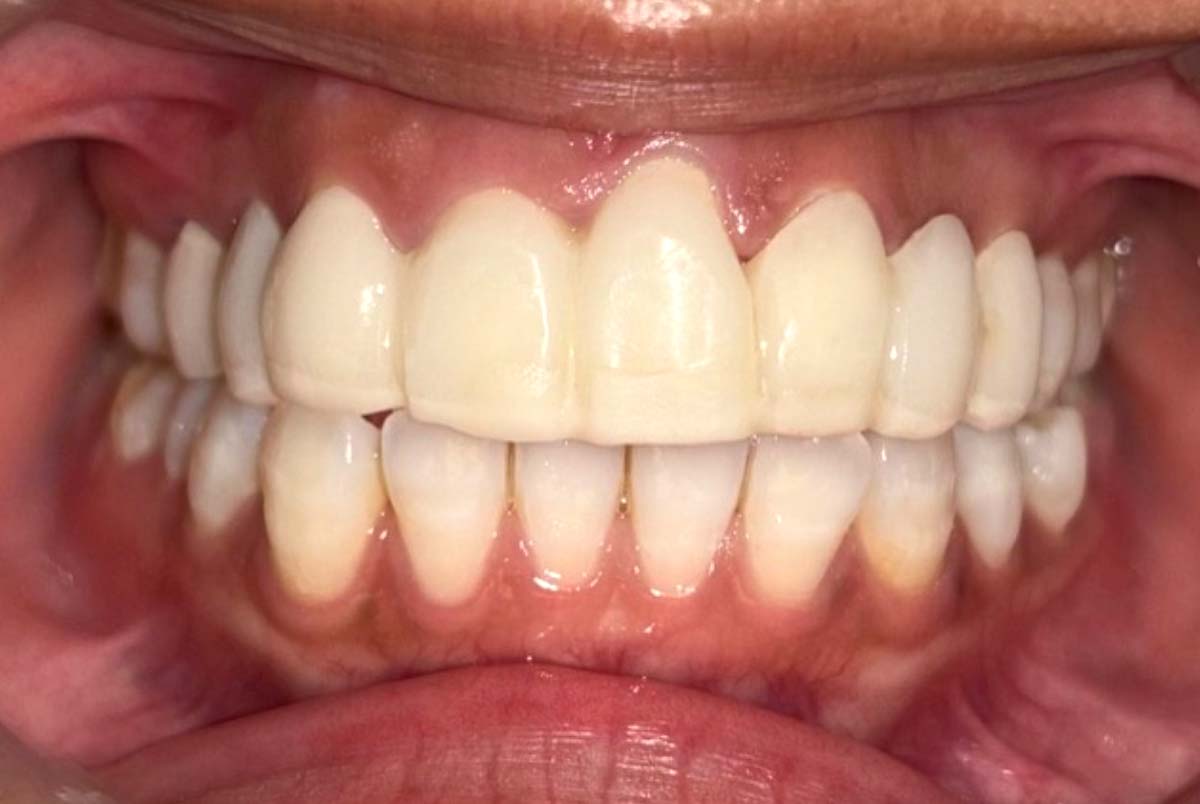

2025年 12月25日

姿勢の変化

2024年 3月 初診時

2024年 10月10日

顔貌の変化